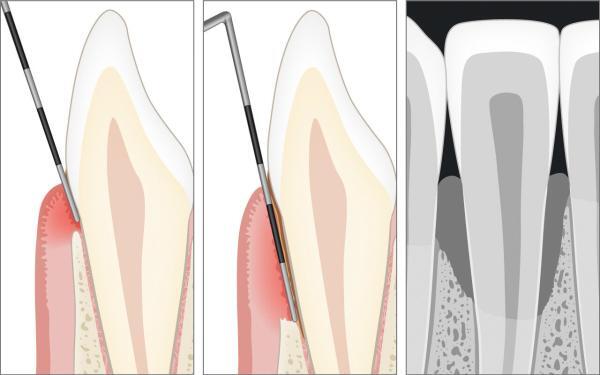

Diagnose der Parodontitis

Die Untersuchung in der Zahnarztpraxis ist die einzige Möglichkeit, den Gesundheitszustand des Zahnfleisches richtig beurteilen zu lassen. Neben der klinischen Beurteilung mit einer Zahnfleischsonde müssen auch Röntgenbilder zur Beurteilung der Knochenverhältnisse hinzugezogen werden.